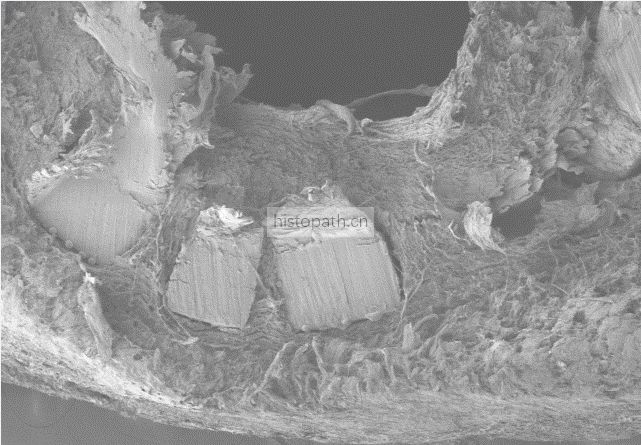

扫描电镜样本准备方法及要求:

动物组织样本

① 1-3min内取样,组织块不超过3mm2,用PBS轻轻漂洗将样本表面的血污,毛发等去掉,将需要扫描的面做好标记(如在对面进行剪角处理)。

② 取材时一定注意避免镊子挤压等机械损伤,刀片要锋利避免挫伤组织。尤其是注意保护扫描面。

③ 组织取下后立即投入电镜固定液内室温固定2h,再转移至4°保存,4°冰袋运输,在保存和运输过程中固定液切勿冷冻结冰。